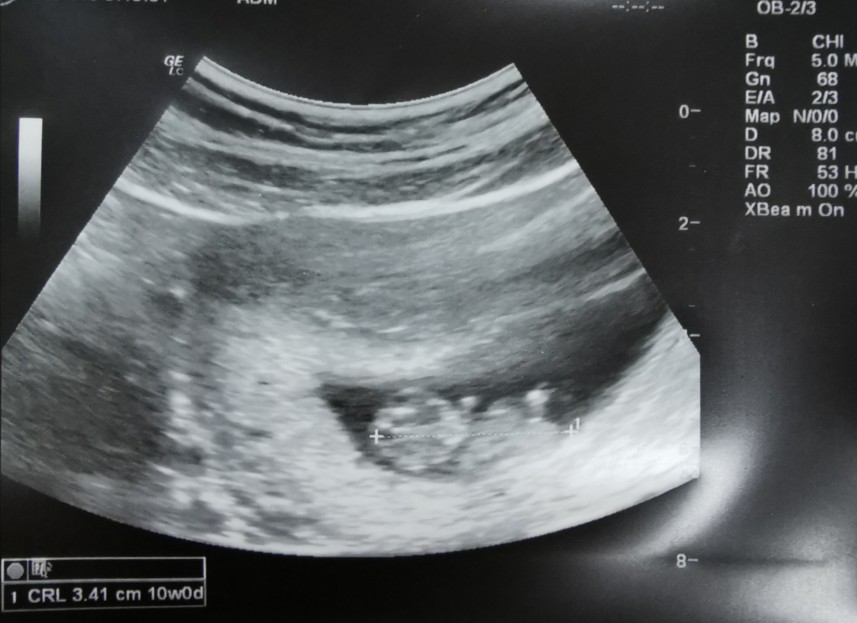

เจอเค้าครั้งแรก ตื่นเต้นมาก 10weeksค่ะ